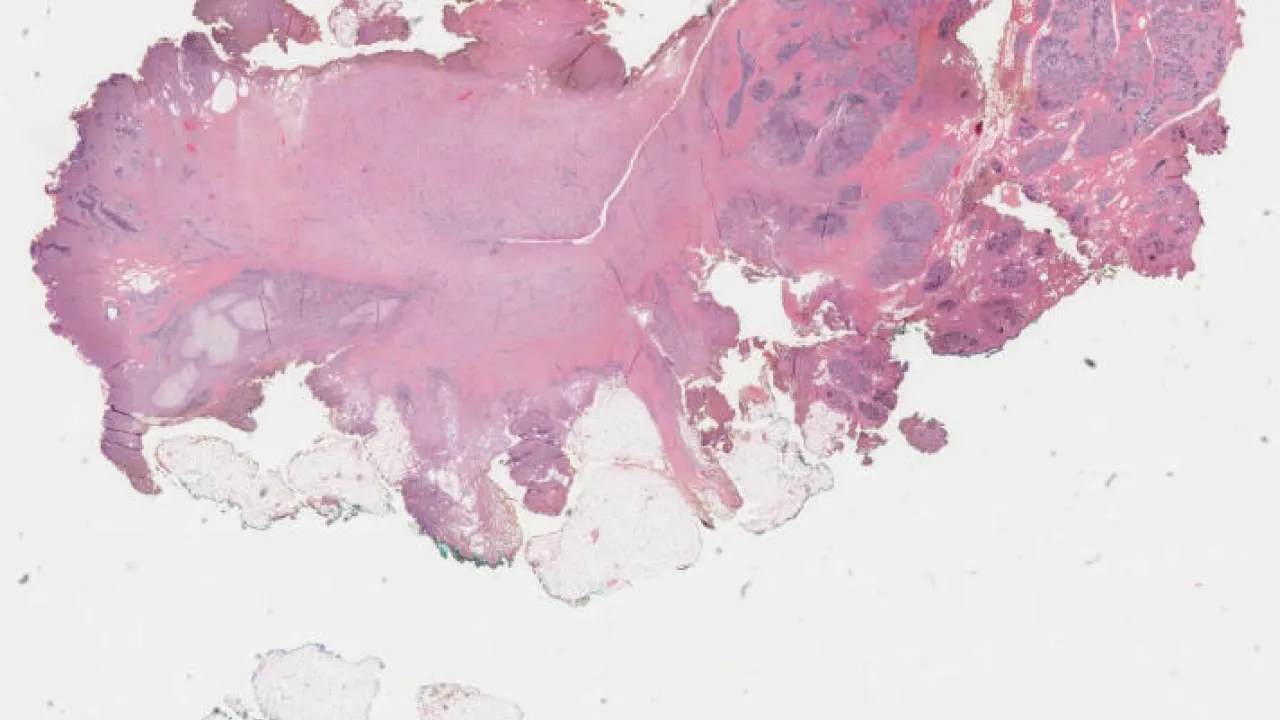

Ovary, Juvenile granulosa cell tumour